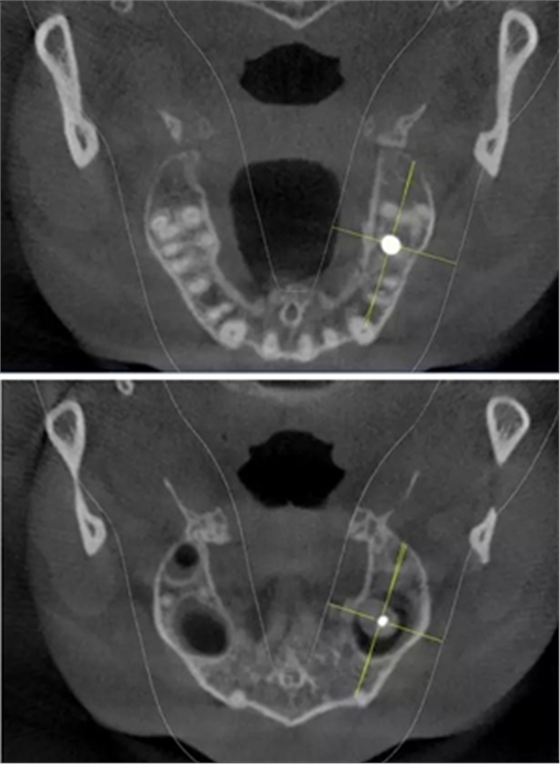

術(shù)前CBCT檢查

骨高度不足,內(nèi)提升的適應(yīng)癥??梢姼]膜致密,厚度均勻。骨高度不足,骨寬度尚可。

術(shù)后CBCT

提升時(shí)相關(guān)步驟可參考下面圖片

可見在完善的檢查和適當(dāng)?shù)墓ぞ哌x擇下可順利完成較復(fù)雜的上頜竇手術(shù)。